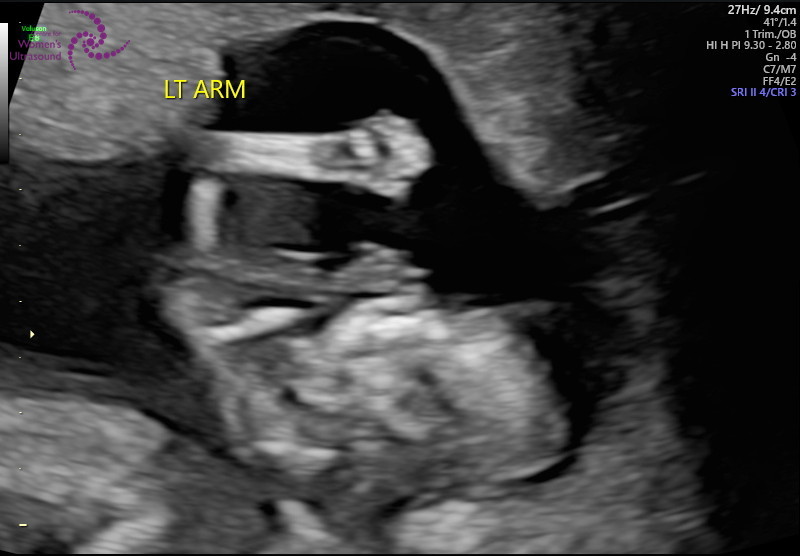

12주 정밀 초음파

젤리곰 탱이를 볼 수 있어요

아기 사이즈 및 기형아 체크

손, 발 길이 등등

자세하게 하나하나 체크하면서

초음파를 보기 때문에 약 40분가량 걸렸어요

화면으로 보는데 너무 신기하더라고요

저렇게 작은데 손, 발이 다 있다니...

울트라사운드라 아이가 초음파 하는데

움직이는 모습도 볼 수 있었어요

이렇게 3d 형태로 아기를 볼 수도 있어서

너무 신기하더라고요